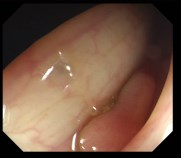

Vision foundation models like the Segment Anything Model (SAM), pretrained on large-scale natural image datasets, often struggle in medical image segmentation due to a lack of domain-specific adaptation. In clinical practice, fine-tuning such models efficiently for medical downstream tasks with minimal resource demands, while maintaining strong performance, is challenging. To address these issues, we propose BALR-SAM, a boundary-aware low-rank adaptation framework that enhances SAM for medical imaging. It combines three tailored components: (1) a Complementary Detail Enhancement Network (CDEN) using depthwise separable convolutions and multi-scale fusion to capture boundary-sensitive features essential for accurate segmentation; (2) low-rank adapters integrated into SAM's Vision Transformer blocks to optimize feature representation and attention for medical contexts, while simultaneously significantly reducing the parameter space; and (3) a low-rank tensor attention mechanism in the mask decoder, cutting memory usage by 75% and boosting inference speed. Experiments on standard medical segmentation datasets show that BALR-SAM, without requiring prompts, outperforms several state-of-the-art (SOTA) methods, including fully fine-tuned MedSAM, while updating just 1.8% (11.7M) of its parameters.